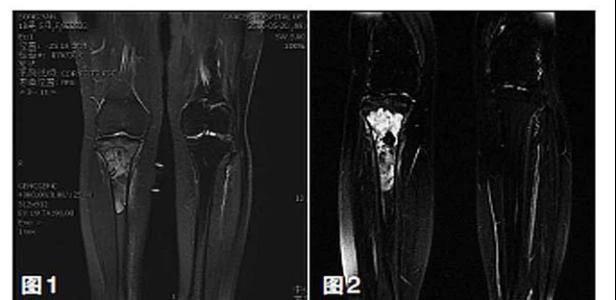

保肢治療指經(jīng)典型骨肉瘤在多學科團隊醫(yī)生共同努力下完成的新輔助化療、保肢手術和輔助化療等一系列治療總稱,其目的是在提高患者生存率的前提下,減少局部復發(fā)、盡量保留良好的肢體功能。肢體經(jīng)典型骨肉瘤保肢治療方法如下圖所示:

新輔助化療的目的是盡早殺滅遠處微小轉(zhuǎn)移灶,縮小腫瘤及周圍炎性水腫反應區(qū),以利于后續(xù)的保肢手術;觀察腫瘤對化療的敏感性,為進一步指定個體化的術后化療方案奠定基礎。骨肉瘤新輔助化療下的保肢治療如下圖所示: